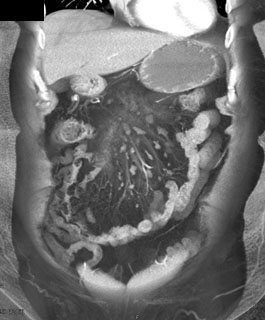

The best dx in this case is

lymphoma

carcinoid tumor

mesenteric panniculitis

mesenteric infarct